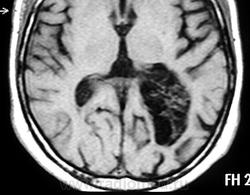

ГМ. Субэпендимома 2. +

Субэпендимома